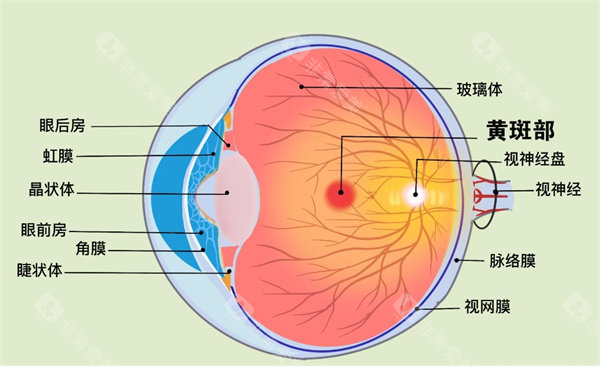

在可靠技术方面,雷医生擅长玻璃体视网膜手术,对复杂性视网膜脱离、糖尿病视网膜病变、黄斑裂孔、黄斑前膜等疾病有独到的治疗经验。

黄斑病变:老年性黄斑变性、黄斑裂孔、黄斑前膜、中心性浆液性脉络膜视网膜病变等

玻璃体疾病:玻璃体混浊、玻璃体积血、玻璃体后脱离等

医院眼底病专科设备可靠,拥有国内外很棒的眼科检查及手术设备,包括光学相干断层扫描仪(OCT)、眼底荧光造影仪、视觉电生理检查仪、超声生物显微镜(UBM)等。